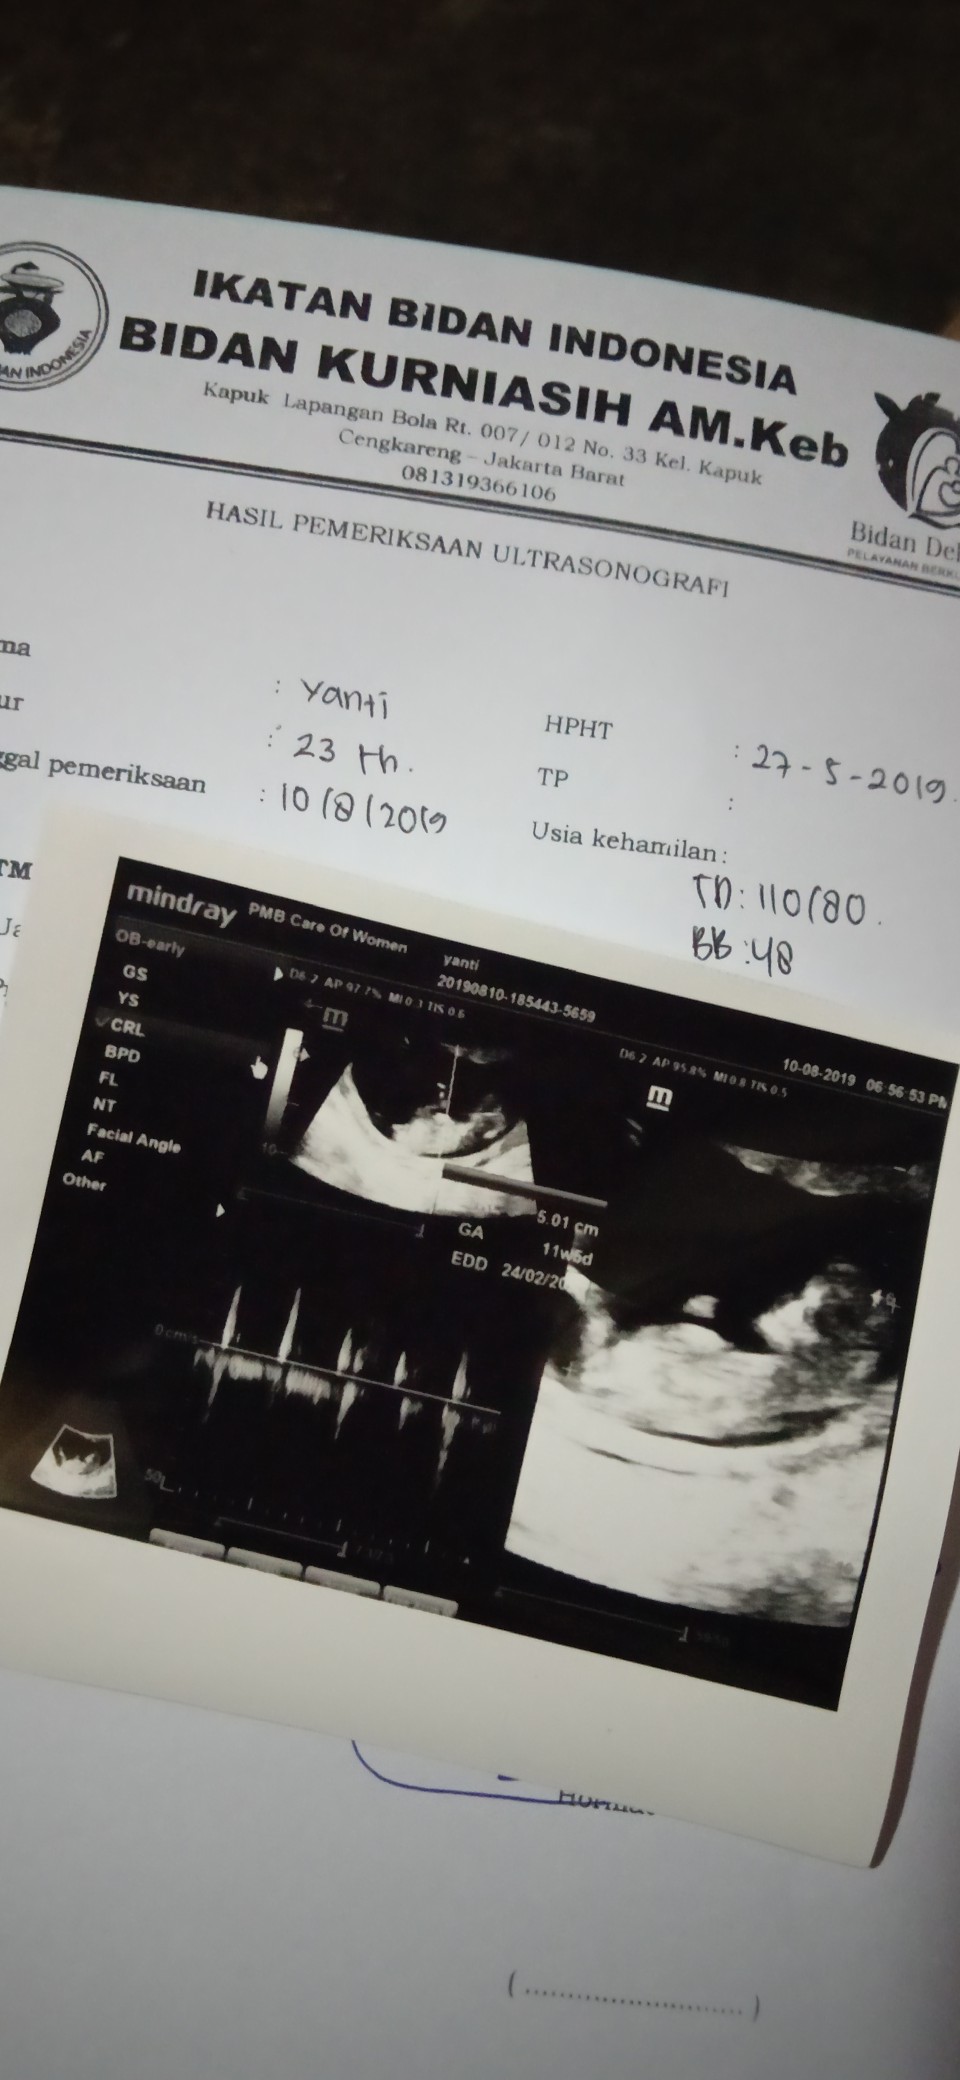

Bun ak mau tanya ni ada ga usg baby girl atau baby boy Nya share Donk bun pengen liat..? Ak jga mau Mtk pendapat usg ku ini baby boy atau girl ya

Ini insyaa allah boy bun, soalnya ada monasnya 😊

klo ini blm kliatan y bun girl atau boy ny